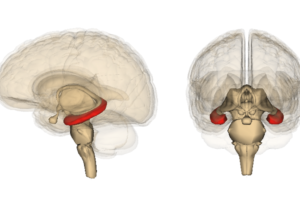

Ciència

Dissenyen uns anticossos per destruir cèl·lules velles i frenar l’envelliment

Dissenyen uns anticossos per destruir cèl·lules velles i frenar l’envelliment

Dissenyen uns anticossos per destruir cèl·lules velles i frenar l’envelliment